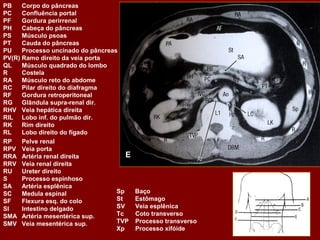

Ac Colo ascendente AP Nível de ar fluido do estômago Ao Aorta Az Veia ázigo CA Tronco celíaco cc Cartilagem costa! CD Dueto cístico CHA Artéria hepática comum CHD Dueto comum CL Lobo caudado fígado D Diafragma DBM Músculos profundos do De Colo descendente D2 Parte descendente do duodeno D3 Parte horizontal do duodeno E Esôfago FL Ligamento falciforme GB Vesícula biliar HA Artéria hepática Hz Veia IMV Divisão da veia mesentérica inf. A IVC Veia cava inferior LC Ramo esq. do diafragma LG Glândula supra-renal esq. LHV Veia hepática esquerda LIL Lobo inf. Esq. do pulmão LRV Veia renal esquerda LK Rim esquerdo LU Ureter esquerdo LL Lobo esquerdo do fígado MHV Veia hepática média P Pâncreas PA Antro pilórico do estômago